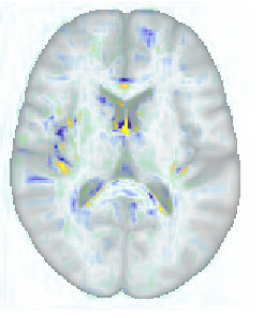

A key advantage of the proposed method over discriminative methods such as RVoxM and SFCN is that, in addition to the discriminative map that it uses to make predictions, it also computes a generative map that expresses the causal effect of the variable of interest on brain morphology. To illustrate why this is important, Fig. 9 shows, for three different training set sizes, the discriminative map computed by our method for predicting age, along with the corresponding discriminative map of RVoXM and the SmoothGrad saliency map (Smilkov et al., 2017) – a generalization of linear spatial maps to nonlinear methods (Adebayo et al., 2018) – of SFCN. The inconsistencies of these maps across both the training set sizes and the different methods, and their overall lack of correspondence with the known neurobiology of aging, illustrate the difficulty of using discriminative maps for human interpretation.

More insight can be gained by examining the proposed method specifically, since it uses disciminative maps that are derived from generative ones. It is worth noting that estimating the generative maps from training data is itself quite stable, since it merely amounts to fitting two basis functions to hundreds of measurements in each voxel (cf. (8)). Furthermore, as illustrated in Fig. 10, the resulting maps are intuitive to interpret, since they show typical age-related effects such as cortical thinning and ventricle enlargement (Fjell et al., 2009; Fjell and Walhovd, 2010). When the discriminative maps are subsequently computed as , however, a strong dependency on the training set size is introduced, because the method explicitly controls the complexity of its noise model in response to the size of the available training set (the bias-variance trade-off of Sec. 4.4). can also capture peculiarities in the data that may be relevant for improving prediction performance, but not for human interpretation. An example of this was shown in Fig. 5, where overall brightness variations and residual MR bias field artifacts were picked up by the noise model. Through , such noise patterns can find their way into , producing hard-to-interpret spatial maps that no longer reflect the expected age-related brain atrophy patterns. This is clearly illustrated in Fig. 4, where the discriminative map is contrasted with the corresponding generative map .